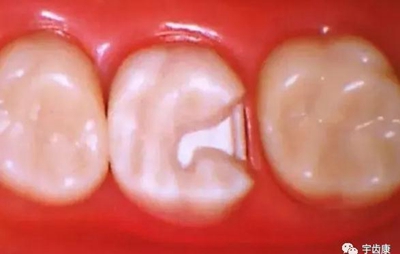

3.基牙具有良好的抗力形

保留活髓及其整體性

保留較多的牙體組織

增加牙體抗力形的措施